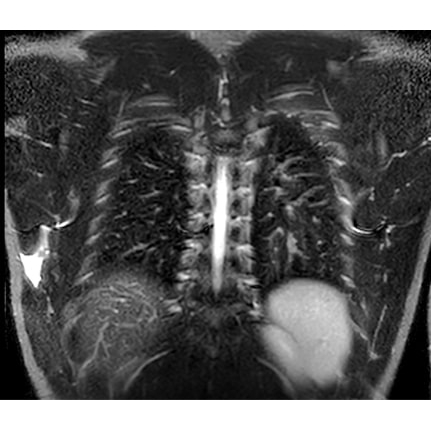

| A Curveball Case Of Armpit Pain In A Pitcher - Page #3 | |||